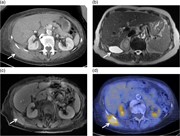

Retroperitoneal calcifying fibrous tumor mimicking an adrenal tumor

Erica C. Prochaska and others

Journal of Surgical Case Reports, Volume 2016, Issue 6, June 2016, rjw049, https://doi.org/10.1093/jscr/rjw049